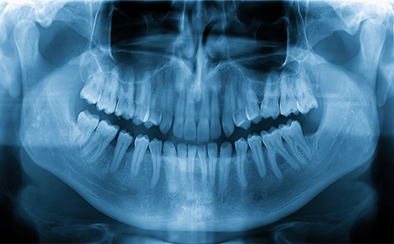

デジタルレントゲン

フィルムを使って出力するレントゲンとは異なり、画像をデータとしてコンピュータ上で処理できる撮影装置です。従来のフィルムレントゲンよりも、明瞭で精密な画像が出力されます。